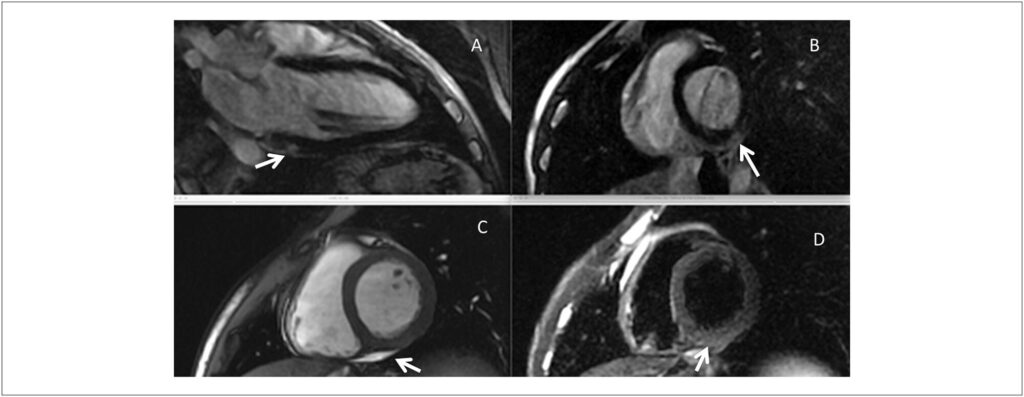

The typical pattern of myocardial injury and subsequent fibrosis in patients with viral myocarditis is subepicardial. However, other patterns of injury and scar, as detected by contrast enhanced magnetic resonance imaging (cMRI), commonly occur, including sub-endocardial injury mimicking the ischemic heart disease pattern, and mid-wall circumferential scar seen more often in patients with advanced disease and dilated cardiomyopathies. In patients with myocarditis, who present malignant arrhythmias in the scenario of a preserved left ventricle (LV) function, it is not uncommon to find the typical subepicardial scar pattern in the presence of normal or mildly abnormal LV systolic function. However, the pathogenesis of sub-epicardial scars in patients with myocarditis accompanied or not by significant LV dysfunction remains obscure.